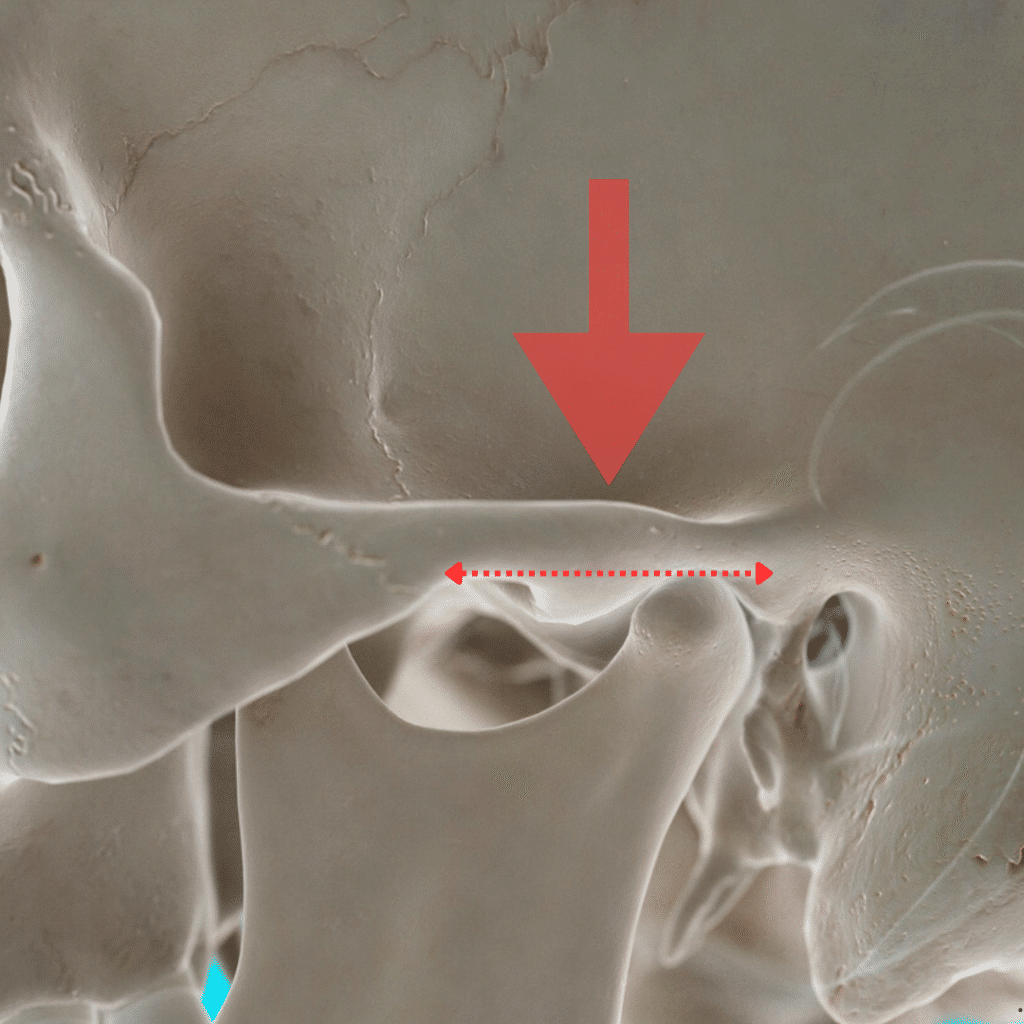

TMJ Disc Displacement

drosmanakinciTMJ Disc Displacement: What It Is and How It’s Treated Temporomandibular Joint (TMJ) disc displacement…

TMJ Disc Reposition

drosmanakinciTMJ Disc Reposition Surgery in Turkey: Restoring Jaw Function for International Patients The temporomandibular joint…